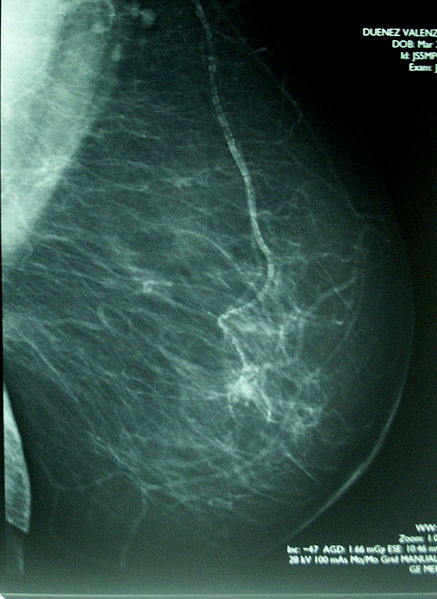

Kada se karcinom dijagnosticira mamografijom, već je prekasno.

Zato su samopregledi jako važni, naročito u zemljama gdje je zdravstvena njega ograničena, kao što je to u Mexicu.